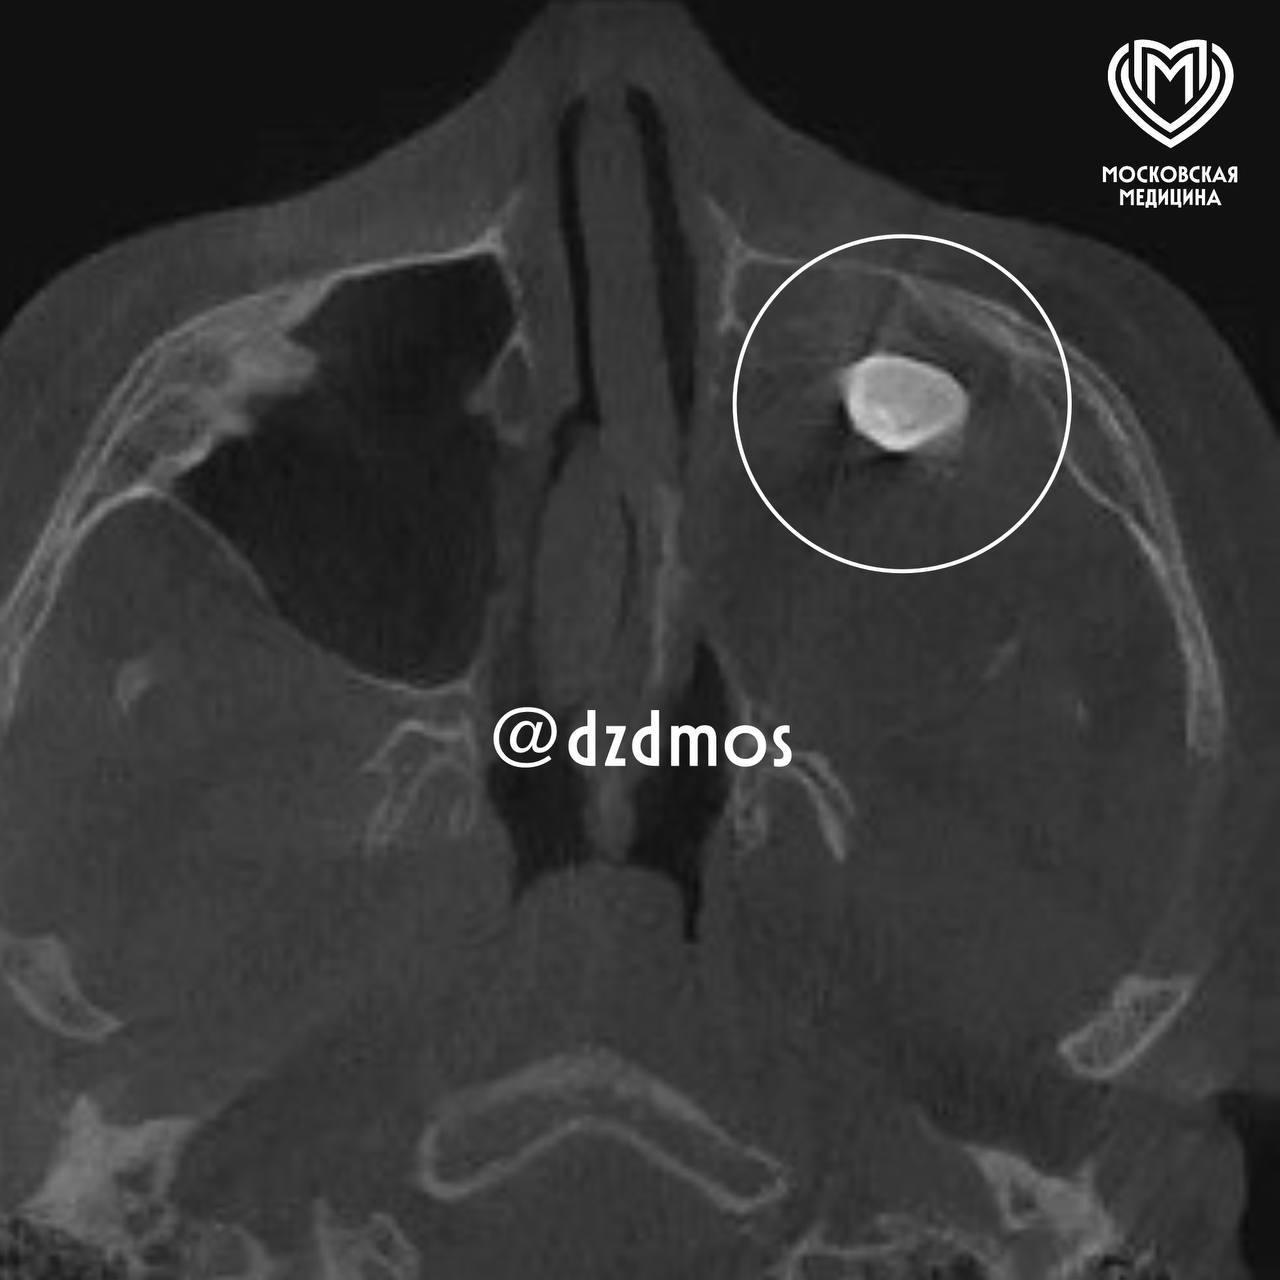

В московскую детскую больницу попал 15-летний мальчик, он жаловался на заложенный нос и асимметрию лица. Медики проверили его и нашли в гайморовой пазухе сформированный зуб.

"Мальчику нужно было провести операцию по Колдуэлу Люку, то есть, обеспечить доступ через верхнюю десну, чтобы вернуть ему возможность нормально дышать. Сделав разрез, врачи обнаружили новообразование, внутри которого и находился зуб", — рассказали в Депздраве Москвы.

Исследование показало, что это тератома — эмбрионально-клеточное новообразование. Обычно в нем могут находиться не только зубы, но и волосы, ногти, кости и мышцы.